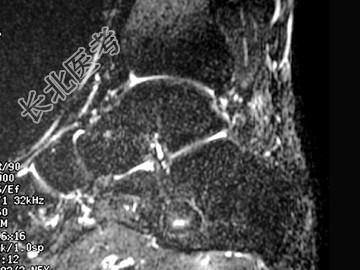

- 单项选择题男,33岁, 无明显症状,结合图像, 最可能的诊断是 ( )

A、骨囊肿

B、骨脓肿

C、未见异常

D、骨內脂肪瘤

E、血管瘤